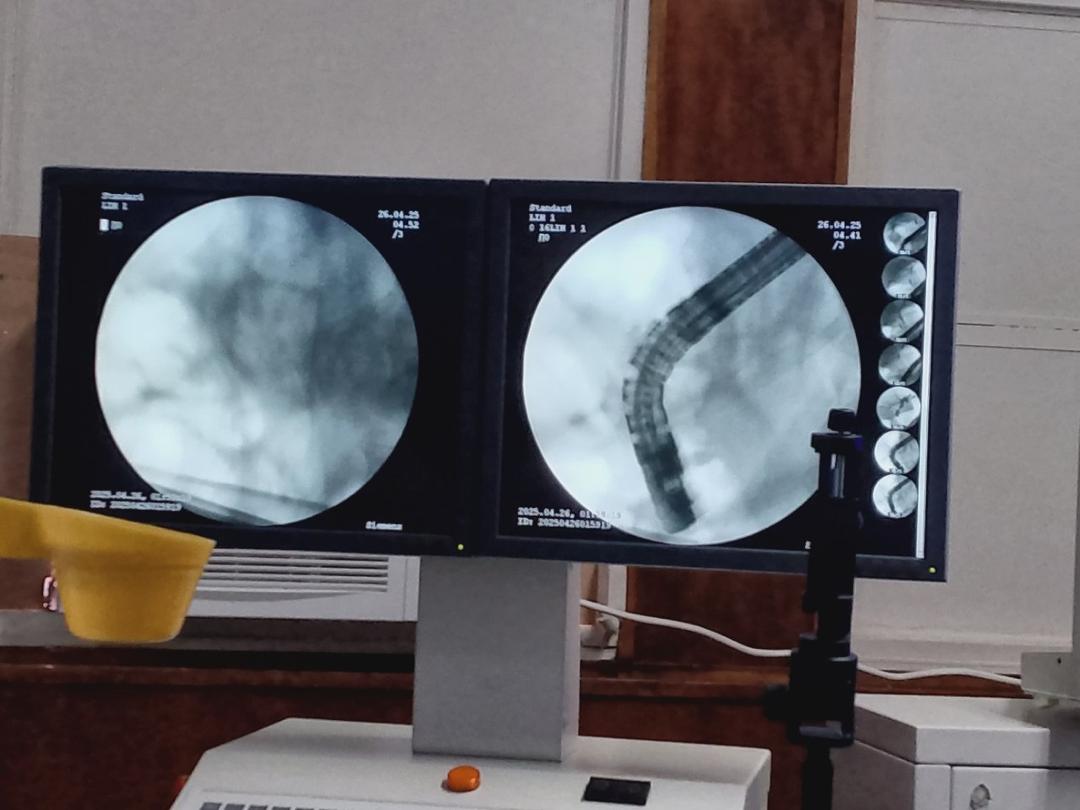

En el Servicio Autónomo Hospital Universitario de Maracaibo (SAHUM) bajó la dirección general de la doctora Oneida Osorio Muñoz, se reactivó -luego de 14 años- la prueba diagnóstica, denominada Colangiopancreatografía Retrógrada Endoscópica CPRE (método para diagnosticar y tratar enfermedades del hígado, la vesícula biliar, los conductos biliares y el páncreas) en el servicio de gastroenterología, específicamente, a cargo del doctor Edgardo Mengual y la participación especial del gastroenterólogo y presidente de la Sección de Endoscópia de la Sociedad Venezolana de Gastroenterología, doctor Jorge Luis Landaeta.

Por su parte, el doctor Mengual explicó «se trata de intervenciones complejas y altamente costosas, debido a que requieren rayos X y procedimientos endoscópicos para desobstruir la vía biliar», detalla nota de prensa.

Durante esta reactivación, se atendieron a 5 pacientes con casos complejos: unos por tumores y otros por cálculos.